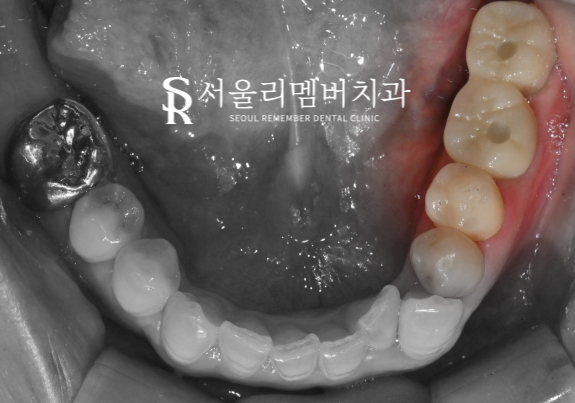

심미, 기능면에서 탁월한 지르코니아 크라운이

구강 내에 자리를 잡고 있는 모습을 볼 수 있네요.

다행히 환자께서도 진짜 치아 색처럼 너무 자연스럽고

예쁘다며 마음에 쏙 들어 하셨는데요.